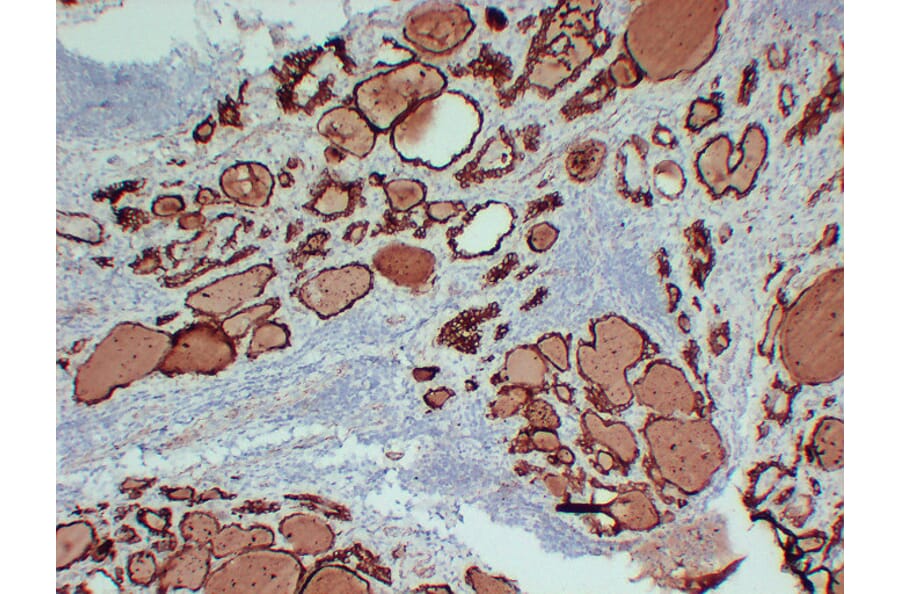

AntiThyroid Peroxidase Antibody [TPO/3695] (A250202)

From www.biosb.com

Thyroid Peroxidase Antibody (EP159) Bio SB Antibodies Thyroid Peroxidase Tpo antibodies may be checked in patients with a high tsh, to. there are different types of thyroid antibodies. Thyroid antibodies can form in. thyroid antibody tests are used to check for different thyroid antibodies that affect your thyroid in different ways. what is the thyroid peroxidase antibodies (tpoab) test used for? Some antibodies destroy thyroid tissue.. Antibodies Thyroid Peroxidase.